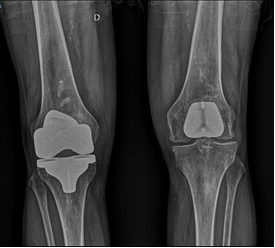

La prótesis total de rodilla es la cirugía más frecuentemente realizada para tratar la artrosis de rodilla. En una intervención con una historia de casi 50 años y es de las cirugías más exitosas que existen afortunadamente. Se realiza la sustitución del hueso desgastado mediante fijación de dos o tres implantes artificiales entre el fémur, la tibia y el fémur. Tras una minuciosa discusión con el paciente, el cirujano decidirá el tipo del implante a usar dependiendo de su edad, forma de los huesos (anatomía), nivel de actividad y calidad de hueso entre otros factores. Un minucioso estudio de planificación clínico antes de la cirugía permitirá la elección de los implantes que se requiere para adaptarlos y corregir la deformidad de la rodilla y de la pierna. Esa planificación hecha más habitualmente con radiografías permite elegir los implantes adecuados y prever los escenarios que pueden encontrarse en el quirófano – un paso imprescindible para el éxito de la cirugía. Los cirujanos de rodilla deben dominar un amplio repertorio de implantes para adecuarlo a cada situación. Los tres tipos de prótesis de rodilla son: la total, la unicompartimental y la femoropatelar.

El que se usa de manera normal con excelentes resultados a largo plazo es la prótesis total de rodilla. Las prótesis de rodilla cementada consisten de tres implantes fijados al hueso con cemento: una arriba en el fémur (muy liso y hecho frecuentemente de Cobalto Cromo), una base implantada dentro de la parte proximal de la tibia tras resecar su superficie (de titanio) y un botón de plástico en la patela. Entre el fémur y la tibia se inserta un plástico de polietileno con propiedades especiales que limita el desgaste o rotura.

|  |  |  |